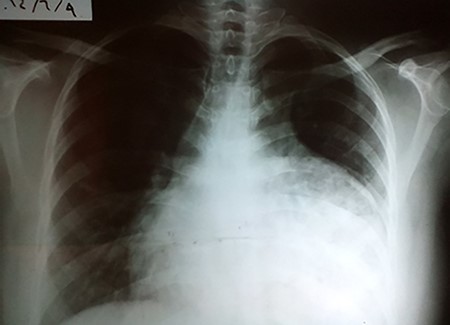

A 35-year-old primigravida female patient complained of mild chest and epigastric pain. Twenty months earlier, she underwent a successful emergent caesarian surgery for preeclampsia, which was performed without complication. Since then, the patient complained of an episodic spasmo-colic pain in the left chest and abdomen that radiated to the left scapula and the upper back. On current presentation, she reported dyspnea and palpitation with sub-sternal heaviness. These symptoms were accompanied by a dry cough, orthopnea and palpitations. No change in bowel movements or any other complaints were reported or evident. She reported no history of surgery except for the cesarean section, which was uncomplicated. She reported no previous trauma, her family history was insignificant and the physical examination was normal. Pfannenstiel incision scar was well-healed with no erythema or drainage, and no tenderness or palpable masses were present around the scar or underneath it. Chest X-ray (Fig. 1) showed an enlarged cardiac silhouette, a closed left costo-diaphragmatic angle and an opacity that covered the left lower border of the heart and the left diaphragmatic dome. The right hemi-thorax was normal. Pleural effusion was suspected and thoracentesis was conducted. The drained fluid labs showed a neutrophilic exudative bloody liquid. Following this, a barium swallow (Fig. 2) was performed, which showed abdominal viscera to be herniated into the thoracic cavity with no other abnormalities. Chest and abdomen computed tomography (CT) scan with contrast (Fig. 3) showed a non-homogeneous opacity in the left side of the thoracic cavity that pushed the heart and other mediastinal components to the right. It was compatible with herniated abdominal viscera, suspected to be either a Morgagni hernia or as a result of a neglected trauma to the diaphragm (although the patient denied any trauma). Surgery was indicated using the thoracic approach. Under general anesthesia, the left chest was entered through the sixth intercostal space, and the thoracic cavity was found to be normal with no signs of hernia. The pericardium was opened and explored; the great omentum and colon were found to be protruded through the diaphragm into the pericardial sac. A defect of 5 cm in diameter was found in the central tendon of the diaphragm (Fig. 4). The adhesions between the pericardium, myocardium and the viscera were released. The viscera were then reduced back into the abdominal cavity through the hernia. The hernia was primarily sewed with running proline suture then covered with 5 × 5 cm proline patch which was supported with a pericardium patch. Finally, the pericardium was partially closed. Three days later, the chest drain tube was removed and the patient discharged in good status. A 2-week follow-up chest X-ray showed no abnormalities and monthly chest X-rays were indicated for a year, and were all normal.

CXR showing an abnormal heart index and opacity that covers the left pleural angle.